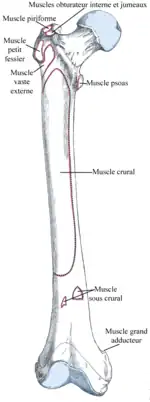

Insertions et origines musculaires

.png)

Fémur gauche, vue postérieure